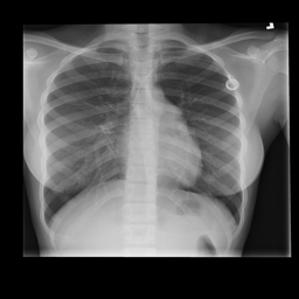

Data: COVID-19 Radiography Database from Kaggle

X-ray images of 4 lung conditions: Normal, COVID, lung opacity (LO), and viral pneumonia (VP)

Each of size 299 by 299 pixels having 10192, 3616, 6012, and 1345 images respectively.